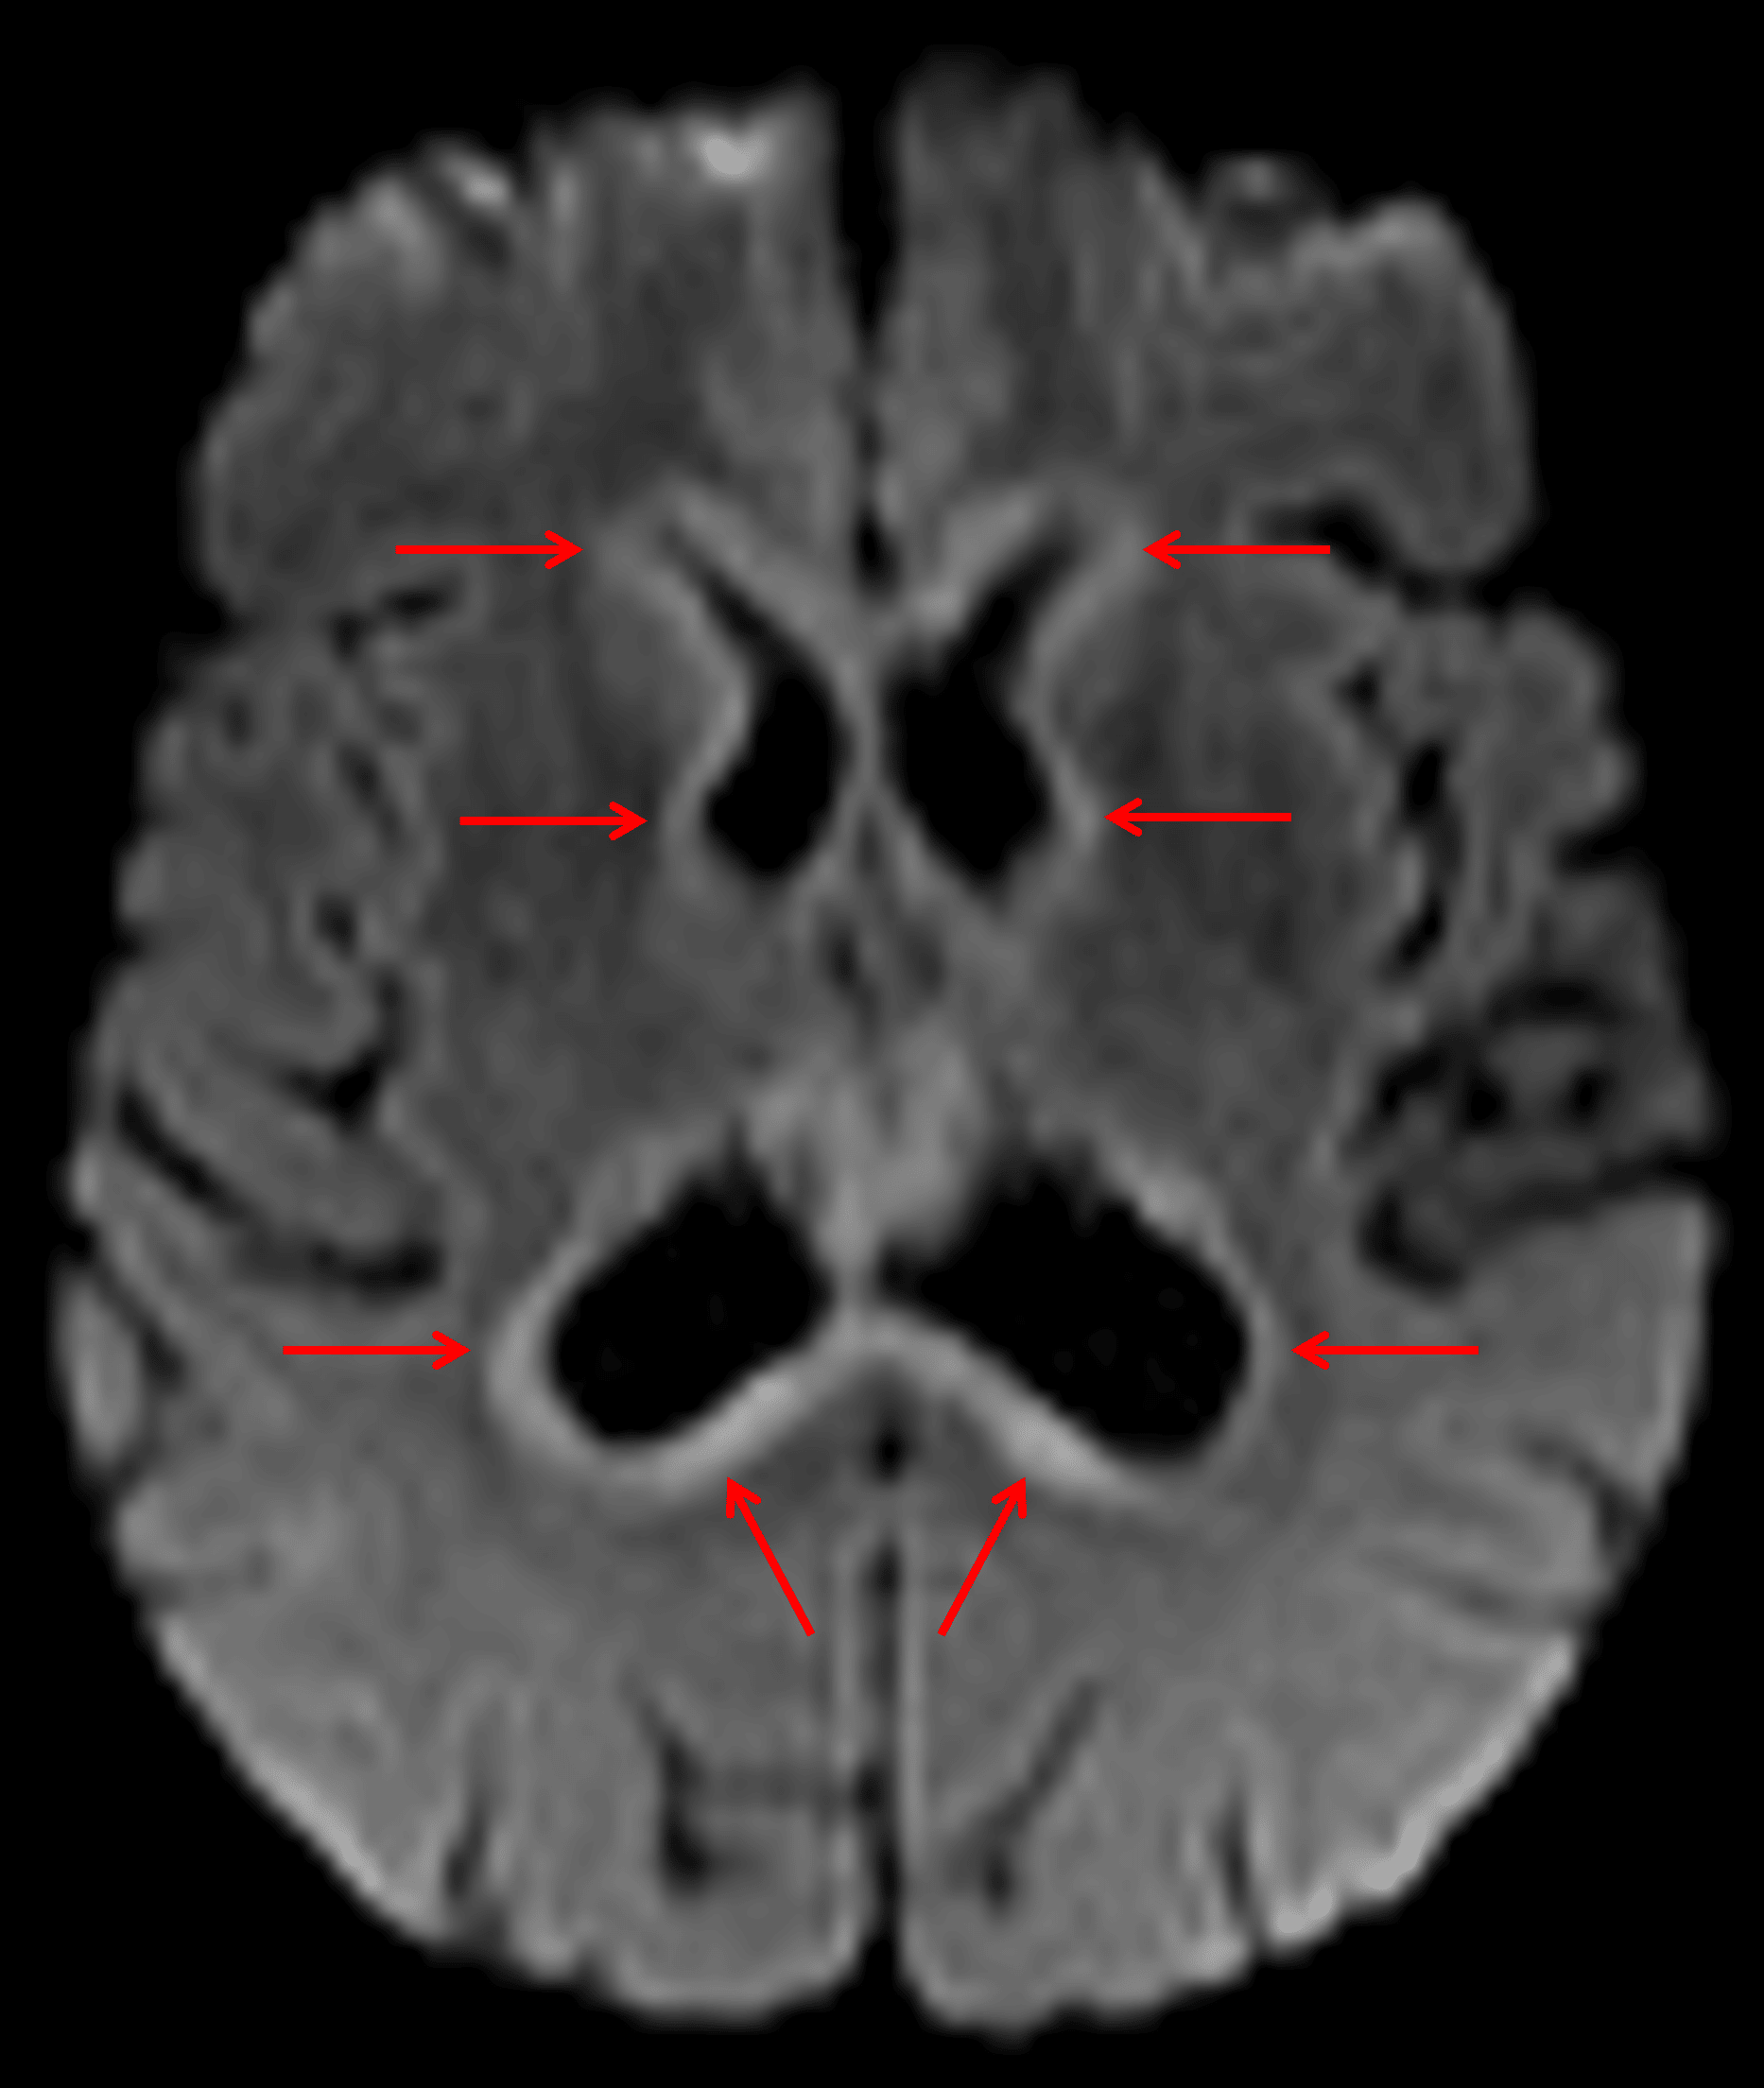

• Thick diffuse restricted diffusion along the margins of the ventricular system with corresponding linear and nodular enhancement

Diffuse rim of restricted diffusion around the ventricles (red arrows), which is a typical appearance for secondary CNS lymphoma.